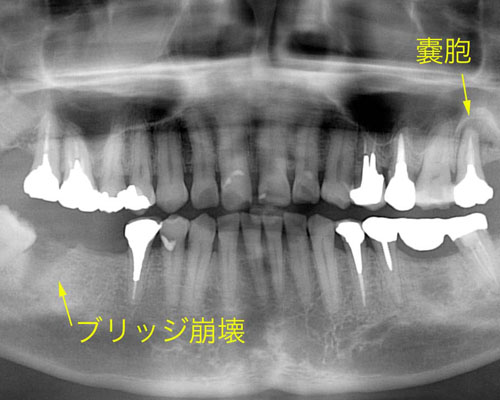

右側下(写真では左)にブリッジを入れていたのですが、歯が割れて抜いたとのことでした。左上にはのう胞といって膿の袋ができています。患者さんのご希望は、インプラントでした。年齢も50台ですので入れ歯は入れたくないとのことでした。

やっと右下にセラミックの歯が入りました。左上にも3本目のインプラントを入れ、もう1本の割れた歯を抜きました。しかし、レントゲンをよく見てみると左側を酷使していた為か、ブリッジの下に虫歯ができて怪しくなっています。